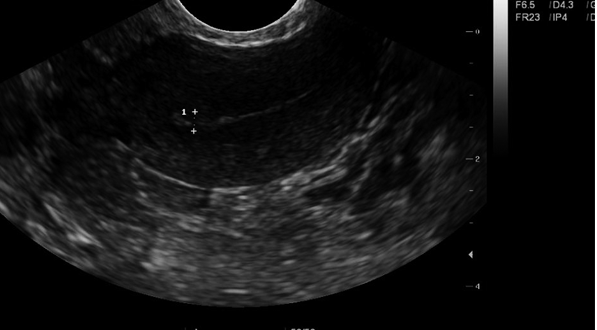

子宫内膜应在长轴或矢状面上测量,理想情况下应在阴道扫描时测量,子宫内膜的整个内层应穿过宫颈管,测量从子宫内膜管的一个基底膜界面到另一个基底膜表面的最厚的回声区域,测量时应注意不要囊括低回声肌层或宫内液。

在月经期和增殖期早期,它是一条薄的、明亮的回声条纹,由基底层组成。在月经期,子宫内膜内可在阴道内发现少量液体; 在增殖期后期表现为三层结构:外回声基底层、中低回声功能层和中央界面的内回声条纹; 分泌期(黄体期)最厚,可达16mm,回声均匀,功能层水肿,与基底层等回声,有通过透射和后声增强注意。子宫内膜厚度正常范围